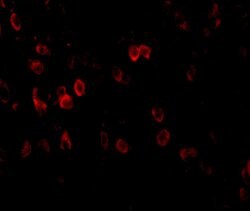

Invitrogen™ Amyloid Precursor Protein Polyclonal Antibody

Brand: Invitrogen™ PA520737

A suggested positive control is rat brain tissue lysate. PA5-20737 can be used with blocking peptide PEP-0851.

Amyloid Precursor Protein (APP) or Amyloid beta precursor protein functions as a cell surface kinesin I membrane receptor, mediating the axonal transport of beta-secretase and presenilin 1. APP is important for neurite growth, neuronal adhesion and axonogenesis. APP is a 100-140 kDa transmembrane glycoprotein that exists as several isoforms resulting from alternative splicing. Proteolytic cleavage of APP by beta- and gamma-secretases results in the generation of beta amyloid, which is the primary component of senile plaques. Senile plaques are one of the major histopathologic features of Alzheimer's disease. Abnormal regulation and processing of APP also plays a role in Down's syndrome, early onset familial Alzheimer's disease, and cerebral hemorrhage.

| Immunohistochemistry, Western Blot | |

| The immunogen is a 18 amino acid synthetic peptide within amino acids 180 - 230 of human Amyloid Precursor Protein (APP). | |

| Human, Mouse, Rat | |